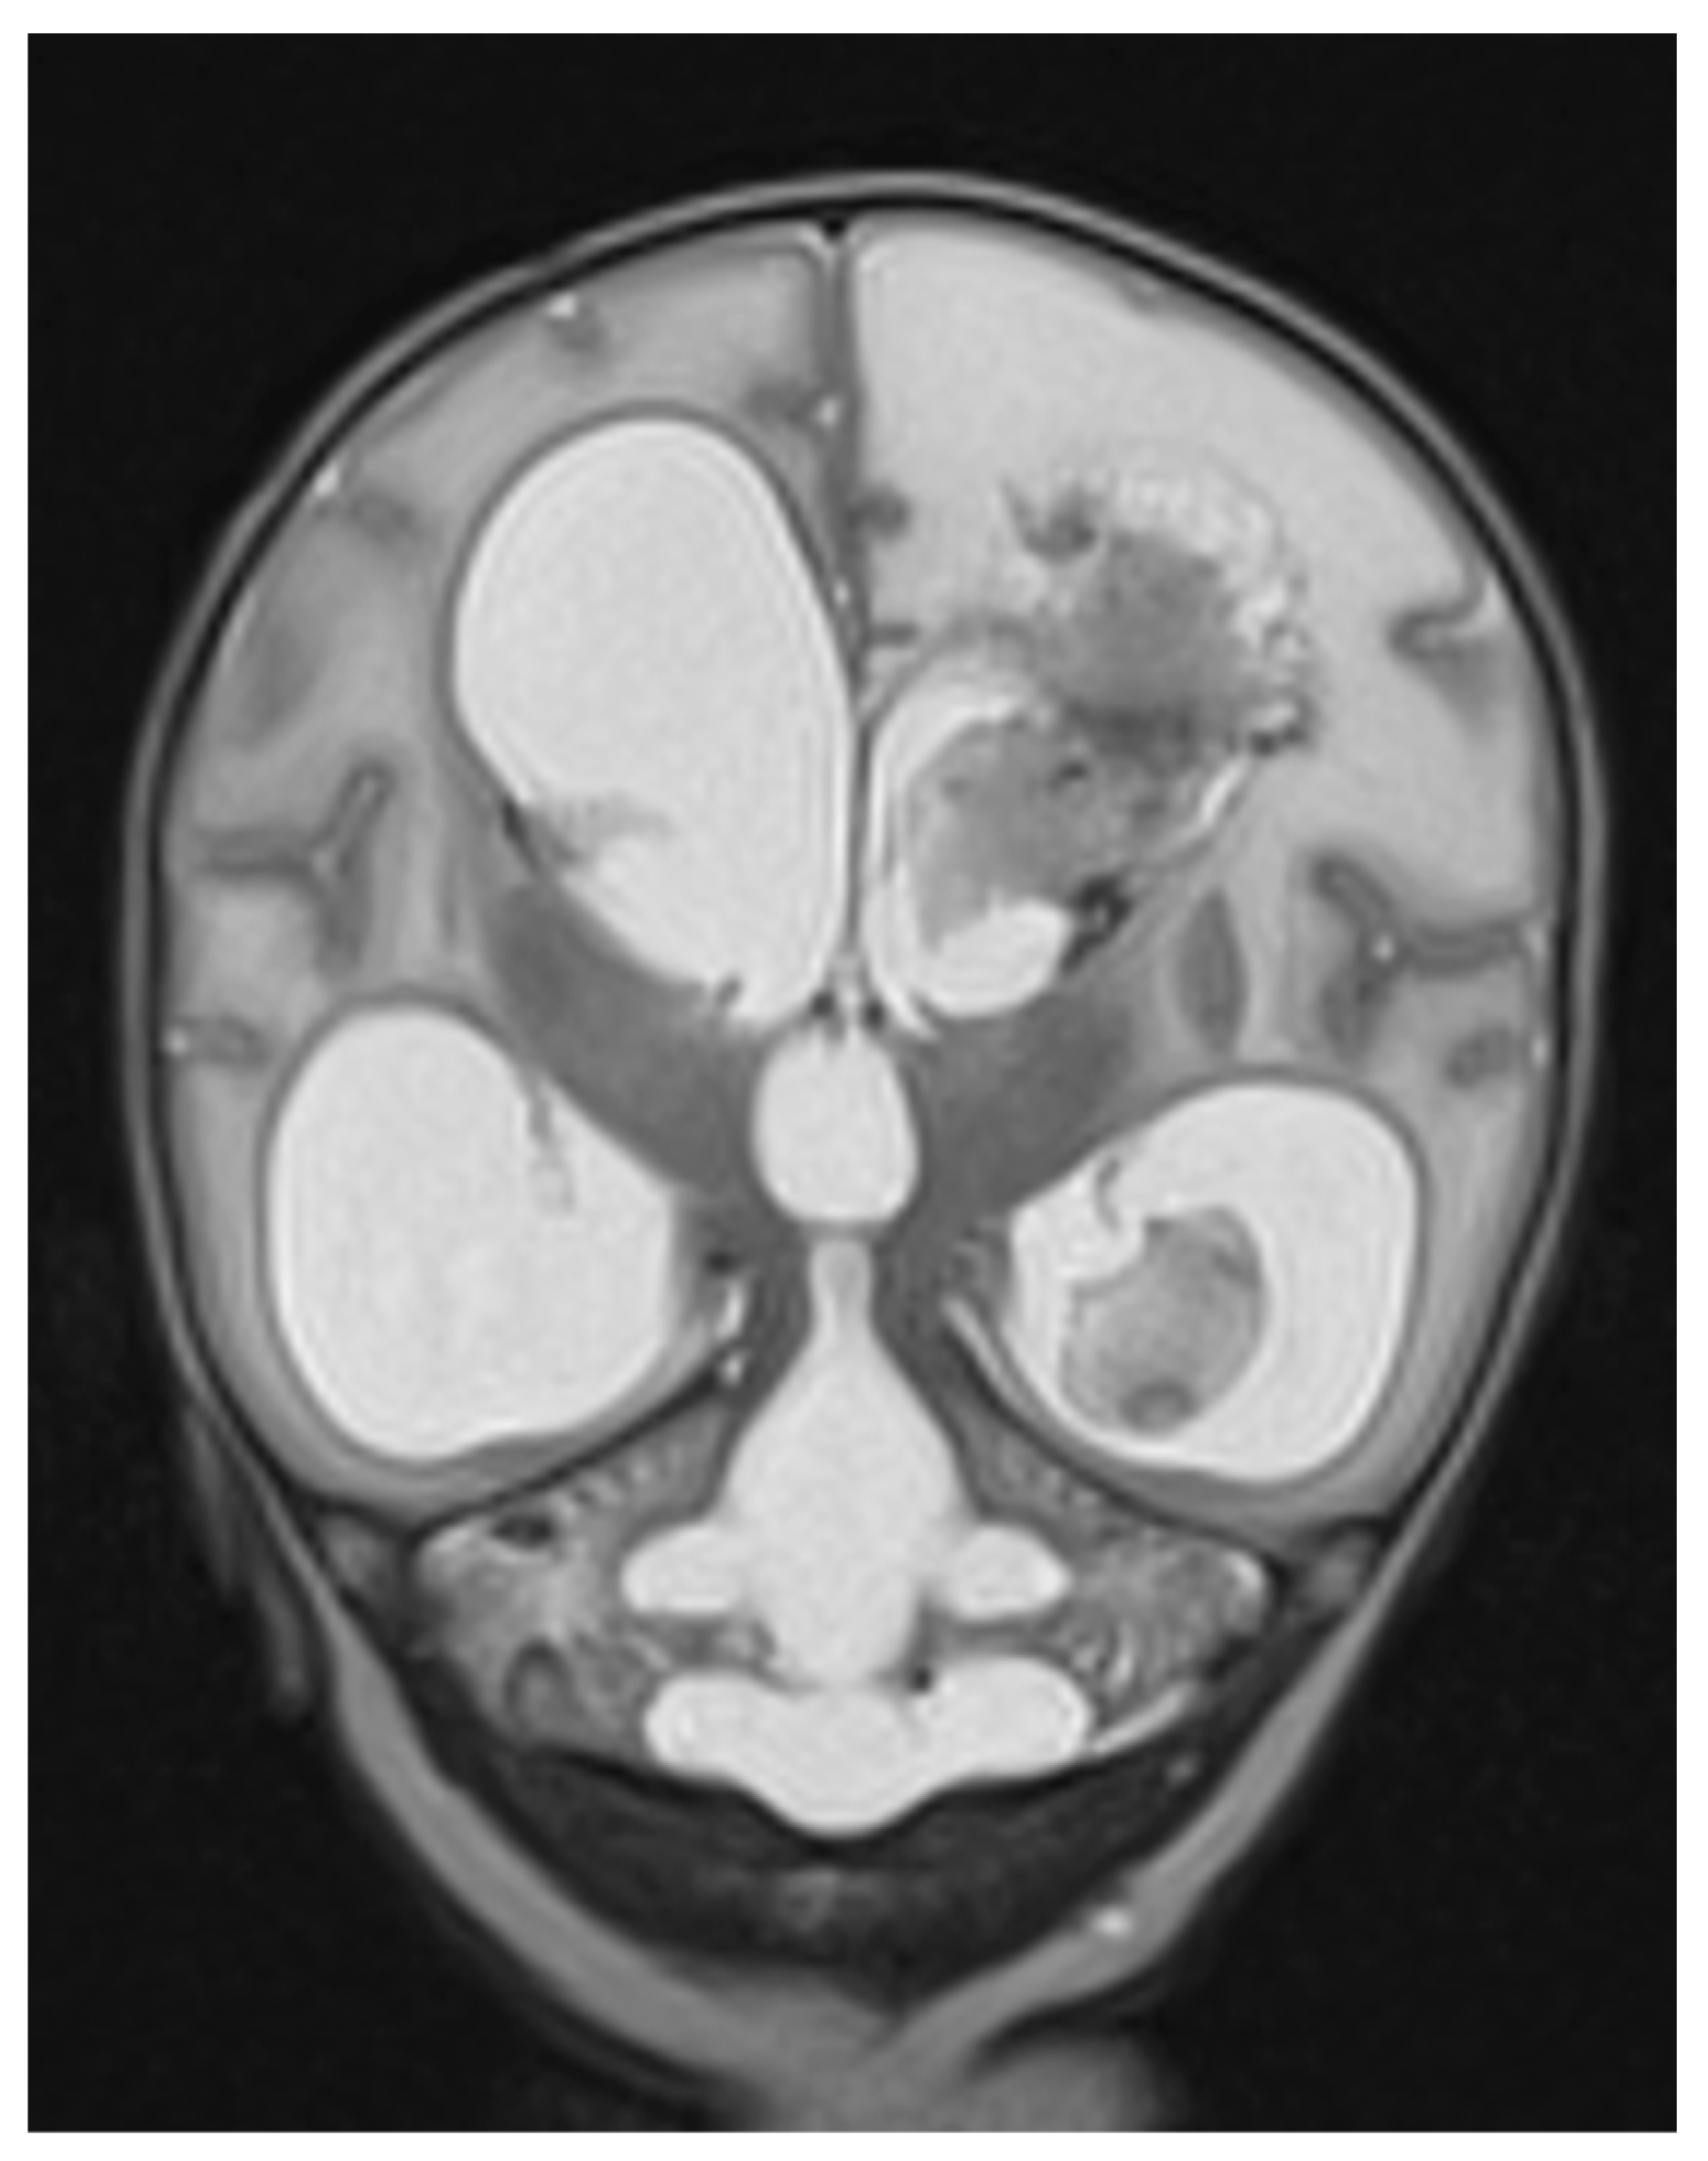

3.3. Diagnosis and Etiology

3.4. Treatment